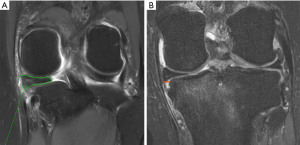

Meniscal root tears were first described in 1991 by Pagnani et al. (1). These tears are currently defined as either a bony or soft tissue avulsion of the meniscal attachment, or as a radial tear within 1 cm of this attachment (2). The medial meniscus (MM) is a crescent-shaped fibrocartilage with a triangular cross-section that covers between 50% and 60% of the medial tibial plateau (3). The MM has much less mobility than the lateral meniscus, in large part due to its attachment to the joint capsule and medial collateral ligament (MCL). The MM is anchored anteriorly and posteriorly to the subchondral bone of the tibia via their respective root attachments (3,4). The MM posterior root (MMPR) attaches posteriorly behind the apex of the medial tibial plateau, 9.6 mm posterior and 0.7 mm lateral to the apex of the medial tibial spine, and 8.2 mm anterior to the most proximal insertion of the posterior cruciate ligament (4,5) (Figure 1). The MM anterior root (MMAR) attaches to the anteromedial proximal tibia, along the intercondylar crest. The center of the MMAR lies 18.2 mm anteromedial to the center of the anterior cruciate ligament (ACL) tibial footprint, 9.2 mm anteromedial to the nearest edge of the ACL footprint, and an average of 7.6 mm anterior to the nearest tibial plateau articular cartilage (5,6). This has been shown to be an average of 9.2 mm anteromedial to the ACL and 27.5 mm anterolateral from the apex of the medial tibial eminence (7).